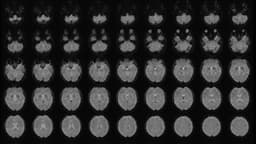

The reason for this alarming trend is that the tiny pollutants can penetrate deep into the lungs, seep into the bloodstream, and even permeate the blood-brain barrier—the natural filter designed to protect the brain. Once inside the brain, these pollutants can cause inflammation and oxidative stress, harming nerve cells and disrupting communication between different brain regions. This can lead to mild declines in memory, attention, and decision-making over time, as well as quicken brain aging and increase the risk of neurodegenerative diseases.